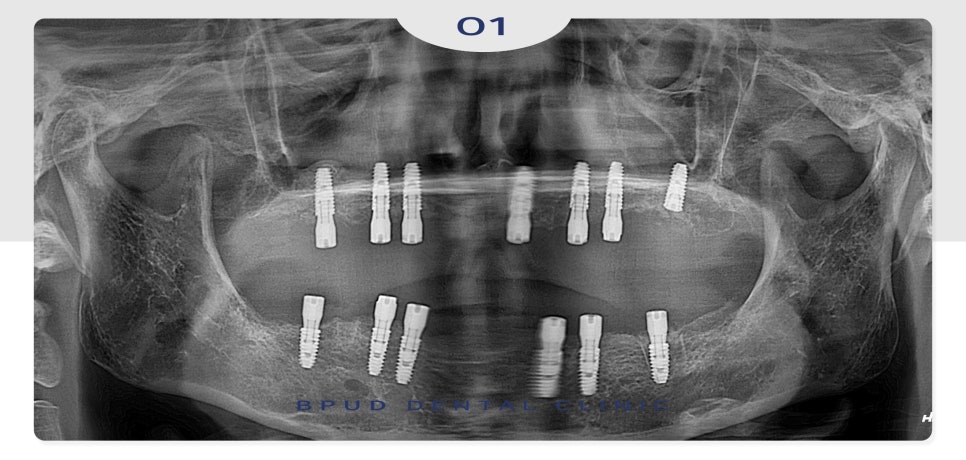

23.10.23

환자분의 경제적인 상황을 고려하여

적은 비용으로 식립을 원하셨으며

전체적인 악궁이 크지 않아

필요한 수만큼만 위쪽 7개, 아래쪽 6개로

인공치근을 식립하였는데요.

수술에 대한 두려움이 크셔서

전체적으로 발치한 후

전악 임플란트와 양쪽 상악동 거상술,

전체 뼈이식을 진행하였습니다.